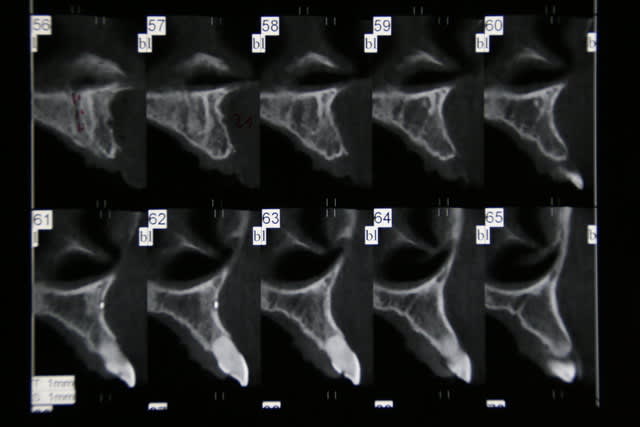

Salut ca y est je me lance, je compte deposé la 12 et 22 et implanter deux implants de 3,8*11. Je compte faire deux lambeaux distincts pour ne pas leser le foramen naso palatin, curetage curette et fraise , implant plutot palatin, assez enfoui , puis comblement bi ooss et mbne ossix, et enfin refermer le tout car pap deja présente pour 11 et 21.

Je n'ai pas bcp d'experience dans le secteur ant , qq implants au plus , ce que je crains c surtout la gestion des tissus pour refermer, si soucis vis cica pas loin...

si j'ai des osteotomes, je peux bien sur les utiliser mais j'ai peur d' etre guide vers l axe de la dent alors que j'aimerai partir plus palatin. quant au biomat c n 'est pas facturé..c juste pour combler le hiatus entre implant et cortic au cas ou l'os de forage ne suffirait pas.

Petit sondage parmi vous osteotome ou pas? Autre petite question si stabilité sup a 20 N : implants enfouis ou non ? Perso je pense les enfouir, mais j'espere pouvoir fermer hermetiquement ( incisions peiostées) le lambeau car je ne maitrise pas les lambeaux perdiculés ou les greffes epithélio conjonctives...

j'ai l'impression en fait que lorsque j'utilise mes osteotomes ,dans ces cas , je maitrise moins les axes ( c peut etre subjectif) ,que les corticales m'impose la place de l 'implant. En general je pointe a l fraise boule, foret pilote et je passe les differents diam . Et puis tu sais en omnipratique les implants ne sont pas quotidiens et donc tu as tjs tendance qd c possible a utiliser le mm protocole pour optimiser tes succés.

bon c fait ce matin , pose des deux implants 12-22, avec un axe un peu particulier dans le sens vestib palatin car proalveolie avec béance ant. J' ai utilise le foret pilote puis osteotome jusqu'a 3.8 de diam ( stabilité primaire 35 pour 22 et inf a 20N pour 12). J'ai fait deux ROG bio oss , ossix car malgré les avoir bien enfoui, la table externe etait vraiment trés fine. J'ai refermé avec difficulté pour trouver l'hermeticité notamment sur 22 ou la racine etait quasiment resorbée. PAP provisoire et feu ... reouvertue prévue dans 6 moi si tout va bien a suivre....